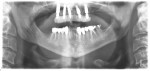

A 36-year-old male patient presented with a highly compromised maxillary dentition comprised of only teeth Nos. 4, 6, 7, 9, 10, 11, and 14 (Figure 1 and Figure 2). This poor condition was the result of only sporadic dental care with extractions and no teeth replacements. Soft tissues had normal contour, and bone profiles were generally sustained and favorable. The patient was excited about having the option to transform his compromised esthetics and function in one visit.

At the initial appointment a panoramic x-ray and periapical x-rays were taken. As part of the protocol, photographs of the patient's head to shoulders were taken, and scans of the teeth and soft tissue were captured with an intraoral scanner (TRIOS 4, 3Shape, 3shape.com). These images were then sent electronically to the implant designer and manufacturer (Osteon Medical, osteonmedical.com) via nexusios.com. Five days later, a virtual smile design (VSD) was provided for review and approval

At the following visit the patient was anesthetized with xylocaine with 1:100,000 epinephrine. Teeth Nos. 4, 6, and 11 were extracted, and immediate implants (Paltop Dynamic Conical, Keystone Dental Group, keystonedental.com) with multi-unit abutments were placed prosthetically correctly with favorable insertion torques in sites Nos. 6 and 11 (Figure 3). Scan gauges (Nexus iOS) were attached to the multi-unit abutments, and a scan was taken to capture the location of the implants with a reference to the remaining teeth with capture of the soft tissues.

Subsequently, teeth Nos. 7, 9, and 10 were carefully extracted with retention of tooth No. 14 to maintain vertical dimension of occlusion with opposing tooth No. 19. An immediate implant with a multi-unit abutment was placed in site No. 4, and additional implants with multi-unit abutments were placed in sites Nos. 8 and 13. All multi-unit abutments were torqued to 30 Ncm.

Scan gauges were then attached to the multi-unit abutments on the remaining implants so that all the implants were now in place with scan gauges (Figure 4). A scan was taken to capture all of the implants and surrounding soft tissue. The scanning protocol calls for scanning left to right, and then a separate scan right to left. These files were then sent electronically to nexusios.com.